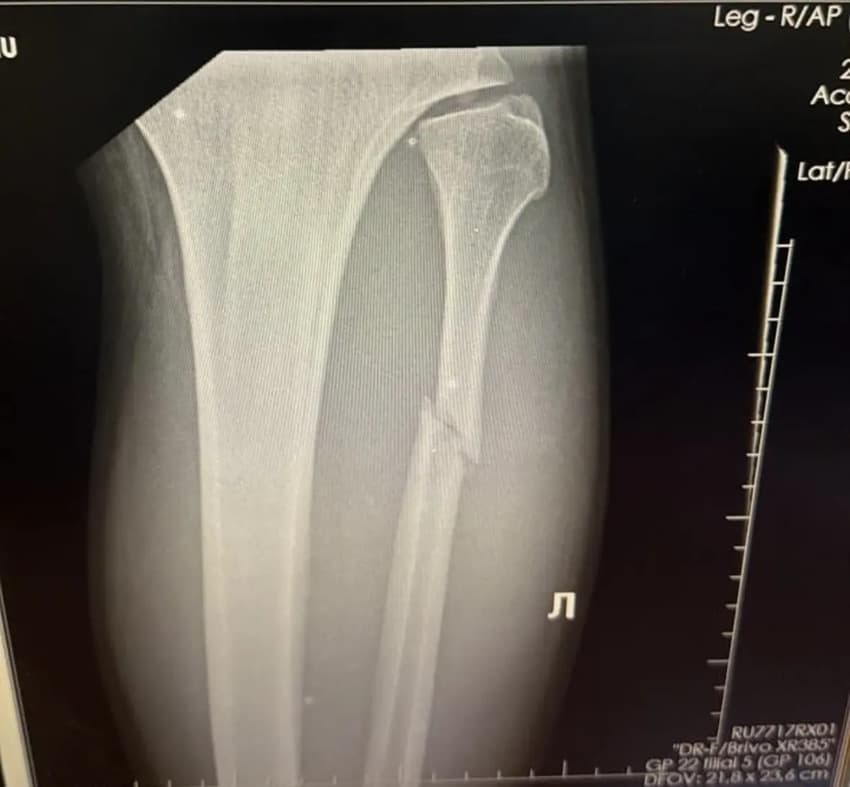

Não demorou para Valter Walker confirmar a vitória no UFC 321, neste sábado (25), contra o inglês Louie Sutherland. Embora tenha feito apenas pouco mais de um minuto de combate, o brasileiro sofreu com um forte chute do adversário e fraturou a perna esquerda. A lesão foi compartilhada pelo peso-pesado através das redes sociais.

Walker não planejava divulgar a gravidade dos ferimentos sofridos na luta contra o inglês. Segundo a publicação, o lutador explicou que está com fortes dores na perna e revelou que ficará de cinco a seis semanas em recuperação. Além disso, expôs uma foto do raio-X da fratura; veja abaixo.

— Eu ia manter segredo, rapaziada. Se viram a live hoje, eu estava de mau humor, pois a perna está doendo demais, mas pediram para revelar. Então, está aí: cinco a seis semanas de recuperação pesada. A primeira semana é a mais difícil, mas, pra falar a verdade, está valendo a pena (risos). Uma vida que vale a pena ser vivida — escreveu Walker.